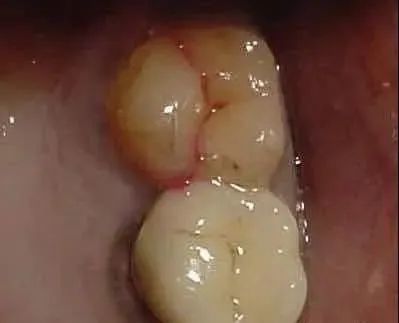

隐裂牙

牙隐裂,又称牙微裂,它是牙冠外表长期遭到慢性损害呈现的小裂纹,一般都表现在磨牙。

隐裂牙比较可怕的是,前期通常没有表现,当裂纹进入到牙体外表下的牙本质层时,就会致使牙酸软、咬物痛苦,到牙髓发作感染时才有自发性痛,而且隐裂牙如果不及时治疗的后果是牙齿劈裂,最终失去这颗牙齿。